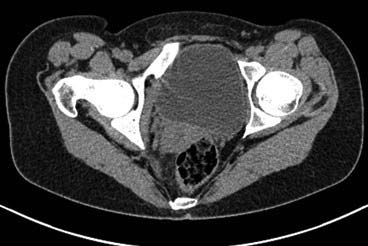

Больная 15 лет. Жалобы: на укорочение правой нижней конечности, хромоту.Анамнез: Со слов болеет с детства, травму отрицает. Ранее за медицинской помощью не обращалась. Последние 2 года отмечает резкое укорочение конечности. Локально: При осмотре отмечается умеренное искривление позвоночника во фронтальной плоскости, умеренная асимметрия лопаток и надплечий. Скошенность таза. Отмечается укорочение правой нижней конечности на 3 см. Движения в тазобедренном и коленном суставах в полном объеме. Нейрососудистых нарушений в периферических отделах нет.

Уважаемый Талгат. Просьба ответить на следующие вопросы: Укорочение у больной анатомическое или функциональное?

Как рентгенологи оценивают состояние крестцово-подвздошных сочленений, не создается ли впечатление о замыкании этого сочленения справа в предшествующие годы, а если это ощущение есть, то что привело к анкилозу этого сочленения. Нет ли по задней поверхности таза в указанной зоне рубца от имевшего место ранее свища?

Наверно целесообразно добавить,что болевого синдрома нет,движения в суставе в полном объёме.Я бы уточнил,что жалобы скорее косметического характера(асимметрия при ходьбе и западение вертельной области справа. Укорочение фигурировало как единственный диагноз в направлении на лечение к нам.Компенсация "укорочения" увеличением высоты каблука обуви не устраняет асимметрию таза и в статике и мало улучшает походку.Вопрос-стоит ли в конкретном случае идти на тройную остеотомию таза и латерализацию вертлужной впадины? Мне представляется,что не стоит.